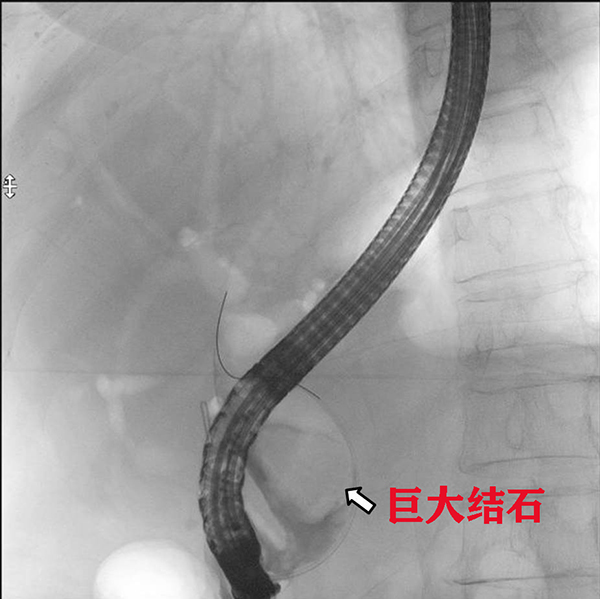

醫(yī)生與患者家屬溝通病情及簽署手術(shù)同意書后,為都奶奶實(shí)施了急診ERCP。術(shù)中,消化內(nèi)科副主任蔡懷陽(yáng)、特聘專家李運(yùn)澤認(rèn)真研讀了患者的CT影像及ERCP術(shù)中造影影像,發(fā)現(xiàn)患者膽總管結(jié)石巨大,但質(zhì)地不硬,可以進(jìn)行ERCP取石。醫(yī)生們靈活采取多種碎石、取石技術(shù),最終成功將結(jié)石全部取出。都奶奶的膽道梗阻得到成功解除,整個(gè)手術(shù)過(guò)程非常順利。

此次從都奶奶身體里取出的膽總管結(jié)石大小約2.5x4.0cm,是醫(yī)院開(kāi)展ERCP十余年來(lái)取過(guò)的最大的結(jié)石,在柳州乃至廣西也很少有成功取出如此巨大膽總管結(jié)石的病例。術(shù)后,患者體溫、血壓立即恢復(fù)正常,術(shù)后第二天即可進(jìn)食、下床活動(dòng),第六天痊愈出院。在這場(chǎng)與死神爭(zhēng)搶生命的戰(zhàn)爭(zhēng)中,消化內(nèi)科成功克服困難,獲得了患者和家屬的信任與感激!